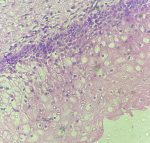

Of the 140 patients, 38 were diagnosed with mild ectocervical dysplasia. The mean AI increased progressively from the lower to the higher grades of CIN. Apoptotic index significantly increases from CIN 3 to carcinomas. Cell counts also increased notably from CIN I to CIN II and III. A sharp increase in AI from CIN 3 to the carcinoma cervix may suggest potential genetic alterations in CIN3 cells, which could drive the malignant transformation from CIN3 to cervical cancer [1,2]. The flaw in the apoptotic pathway enables cells to multiply despite the presence of genetic mutations. Therefore, AI can be used to evaluate the importance of apoptosis as an indicator of proliferation [3]. Mean AI was calculated using descriptive statistics. Of these, 53 cases had squamous metaplasia, 38 had mild dysplasia (Figure 1), 19 had moderate dysplasia (Figure 2), and 14 had severe dysplasia (Figure 3), 16 cases of malignancy (Figure 4) were evaluated (Table 1). In squamous metaplasia (Figure 5), the mean AI was 1.03, while in mild cervical dysplasia it was 1.51. For moderate cervical dysplasia, the mean AI was 3.06, and for severe dysplasia, the mean AI was 5.23. In cases with overtly malignant cervical lesions, the mean AI was 7.35. The mean AI showed a progressive increase with higher dysplasia grades. The most common age groups for squamous metaplasia (19 cases), mild dysplasia (17 cases), and moderate dysplasia (7 cases) were between 35 and 44 years, whereas for severe dysplasia (5 cases), it was between 55 and 64 years. The most common age group for malignancy (9 cases) was 45-54 years (Table 1). The Ki-67 proliferation index in malignant cases ranged from 70% to 80% (Figure 6), whereas in non-malignant cervical lesions, it was between 1% and 2% (Figure 7). Squamous metaplasia, mild dysplasia, moderate dysplasia, severe dysplasia, and malignancy all showed significant, p-values (Table 2). To confirm findings of dysplasia in mild and malignant tumors, Ki-67 staining was performed. Ki-67 expression correlated with the apoptotic index (Table 3). A higher AI is indicative of high-grade epithelial dysplasia. AI can be utilized as a prognostic marker for the follow-up and monitoring of patients with epithelial dysplasia. AI serves as both a diagnosis and prognosis marker in patients with epithelial dysplasia.

Figure 1: H&E; x 400, mild dysplasia in ectocervix